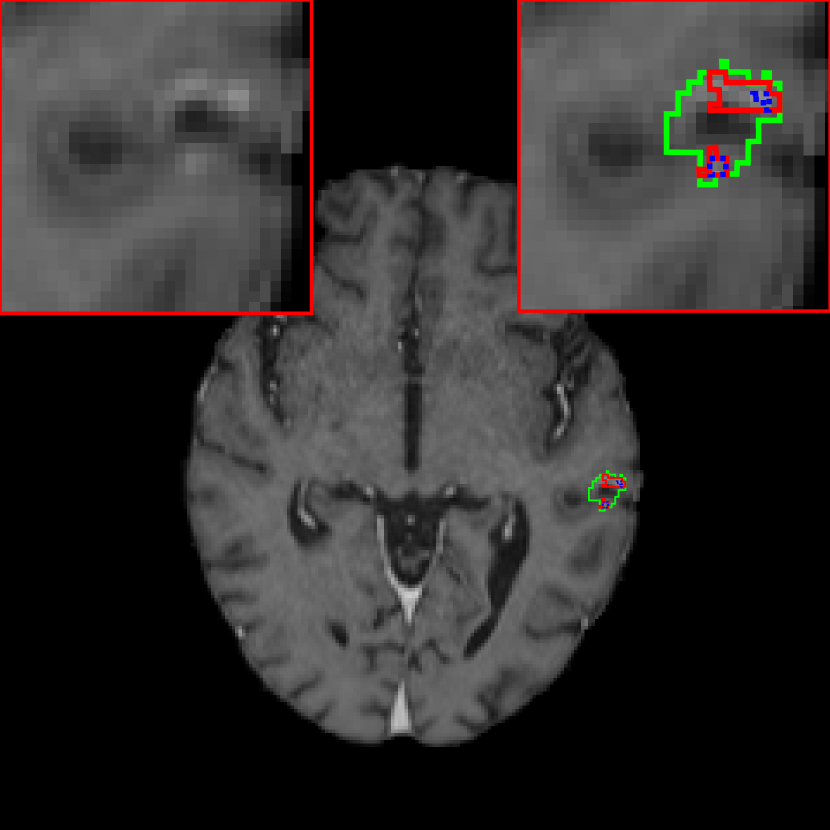

III.B. Results of DeepMedic+ using temporal prior

Fig. 5 is an example where temporal prior information is beneficial for metastasis identification. With an additional path for the prior volume, the red region in Fig. 5, as well as the other two cases in Fig. 5, is detected correctly. The sensitivity and precision for DeepMedic+ with the JVSS loss (α=0.995𝛼0.995\alpha=0.995 and α=0.5𝛼0.5\alpha=0.5) together with the temporal prior, i.e. senssubscriptsens\mathcal{M}_{\text{sens}} and specsubscriptspec\mathcal{M}_{\text{spec}} respectively, are displayed in Tab. 1. For α=0.995𝛼0.995\alpha=0.995 (senssubscriptsens\mathcal{M}_{\text{sens}}), the total number of FP metastases is reduced from 247 to 158, where 36.0%percent36.036.0\% ((247 - 158)/247) FP metastases are reduced. The average FP rate per patient is reduced from 2.40 (247/103) to 1.53 (158/103). As a trade-off, the sensitivity has a slight decrease from 0.946 (263/278) to 0.932 (259/278), with only 4 more FN metastases. Note that some of the test volumes are first scans without temporal prior volumes. If we exclude such volumes, the number of FP metastases decreases from 180 to 100 with the help of temporal prior, which is about 44.4% (180 - 100)/180 less, where 3 instead of 4 more FN metastases are observed. The average FP rate per patient is reduced from 2.54 (180/71) to 1.41 (100/71) for those with prior scans. For α=0.5𝛼0.5\alpha=0.5 (specsubscriptspec\mathcal{M}_{\text{spec}}), the sensitivity is slight worse than that of baselinesubscriptbaseline\mathcal{M}_{\text{baseline}}. However, the precision is as high as 0.996 (234/(234 + 1)) with only one FP metastasis. The FP case is displayed in Fig. 7, where the current main image together with its temporal prior and posterior images are displayed. The difference image between the main image and the temporal prior image is displayed in Fig. 7(c), where the area indicated by the arrow has larger difference. That is why specsubscriptspec\mathcal{M}_{\text{spec}} regards this region as a metastasis. However, after checking its posterior image (Fig. 7(d)), no grown metastasis exists. Therefore, we regard the detection in Fig. 7(b) as FP. But we cannot eliminate the possibility that a real metastasis has regressed at the segmented region before the posterior scan.

For segmentation accuracy, the mDSCs for all the TP metastases are displayed in Tab. 1. In general, the mDSCs are around 0.8. With a smaller α𝛼\alpha value, the mDSC value gets slightly smaller. The segmentation boundaries of three exemplary metastases are displayed in Fig. 8. Green boundaries are manual reference segmentation boundaries, while red (α=0.995𝛼0.995\alpha=0.995) and blue (α=0.5𝛼0.5\alpha=0.5) boundaries are segmentation boundaries of senssubscriptsens\mathcal{M}_{\text{sens}} and specsubscriptspec\mathcal{M}_{\text{spec}}, respectively. In Figs. 8(a) and (b), all the three boundaries have good consistency, with DSC values larger than 0.9. These two segmentation results are general cases for metastases larger than 0.1 cm3. Fig. 8(c) is one example where DeepMedic+ achieves lower DSC values. The tumorous region in this case is difficult to define in single-sequence data as some part of the whole tumor has necrosis after treatment. In addition, the active parts, which are enhanced by contrast agents, are separated in many axial slices. Therefore, senssubscriptsens\mathcal{M}_{\text{sens}} and specsubscriptspec\mathcal{M}_{\text{spec}} both segment the active parts as two separated metastases. As a consequence, the DSC values are low. Nevertheless, senssubscriptsens\mathcal{M}_{\text{sens}} segments the active parts better than specsubscriptspec\mathcal{M}_{\text{spec}}. Tab. 1 indicates that senssubscriptsens\mathcal{M}_{\text{sens}} achieves better mDSC values than the baseline DeepMedic, while specsubscriptspec\mathcal{M}_{\text{spec}} is slightly worse. Since the union of senssubscriptsens\mathcal{M}_{\text{sens}} and specsubscriptspec\mathcal{M}_{\text{spec}} segmentation masks is used in our ensemble learning, the good segmentation of senssubscriptsens\mathcal{M}_{\text{sens}} is preserved.

Refer to caption

(a) 0.941, 0.916

(b) 0.910, 0.910

(c) 0.596, 0.133

Figure 8: Segmentation boundaries of three exemplary metastases. Green boundaries are manual reference segmentation boundaries, while red solid and blue dotted boundaries are segmentation boundaries of senssubscriptsens\mathcal{M}_{\text{sens}} and specsubscriptspec\mathcal{M}_{\text{spec}}, respectively. The DSC values of each metastasis volume are displayed on the left and right in the subscaptions for senssubscriptsens\mathcal{M}_{\text{sens}} and specsubscriptspec\mathcal{M}_{\text{spec}}, respectively. Zoom in for better visualization.